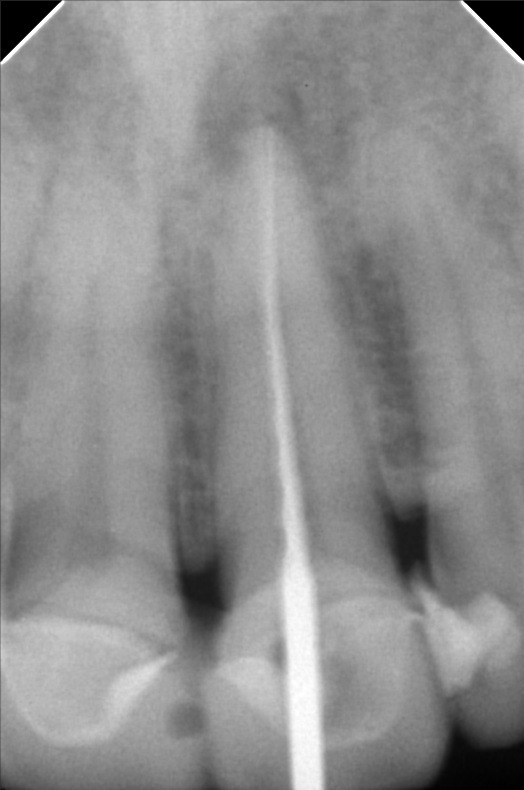

- 01/31/21 OP xray 11&21 #21 with periapical abcess 02/07/25 White and Yellow file patent 25mm apexcal ICF

- yu.jpg